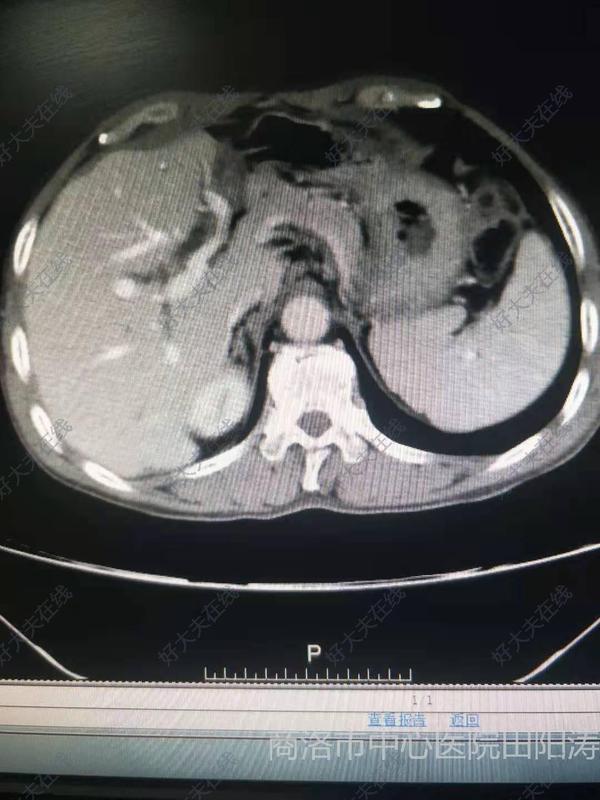

治療前 患者系急性膽管炎,肝內(nèi)外膽管多發(fā)結(jié)石。術(shù)前增強(qiáng)CT檢查提示:肝內(nèi)結(jié)石分布于左肝管,且伴膽管狹窄。MRCP檢查提示:膽囊結(jié)石。膽總管結(jié)石。肝內(nèi)結(jié)石分布于左肝管,且伴膽管狹窄。 治療中 腹腔鏡解剖性左半肝切除術(shù)+膽囊切除+膽總管切開取石、膽道鏡探查取石、T管引流術(shù)。 治療后 治療后6天 腹腔鏡解剖性肝切除術(shù),具有創(chuàng)傷小,恢復(fù)快特點(diǎn)。術(shù)后EARS,患者快速康復(fù)出院。花費(fèi)少,康復(fù)快。